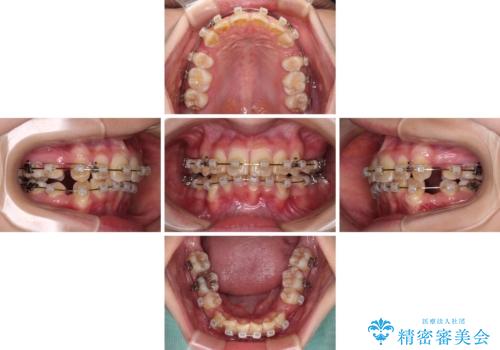

【モニター】出っ歯と八重歯 抜歯矯正でスッキリとした口元に

- 前方に飛び出した前歯と、下顎の八重歯を気にして来院された患者様です。

口元の突出感を改善するため、上下左右の第一小臼歯4本を抜歯し、ワイヤー装置にて矯正治療を行うこととしました。